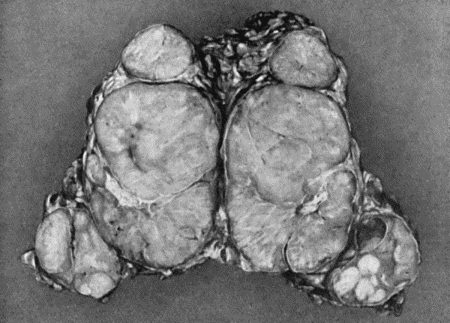

54.Fibro-myoma of Uterus 196

55.Recurrent Sarcoma of Sciatic Nerve 198